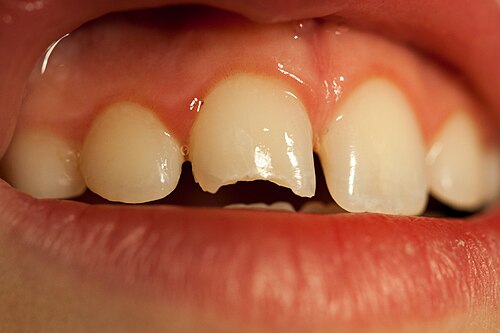

🦷 씹을 때 시리고 아프다면? 상아질 손상

법랑질에 이어 상아질까지 손상된 경우, 아래에 얇게 붉은색 치수(신경)이 비쳐보이는걸로 보아 신경까지는 진행이 안된걸 알 수 있습니다(출처: https://en.wikipedia.org/)

깨진 후

찬물에 시리고 🥶

씹을 때 찌릿하다면 😣

이미 상아질(dentin)까지 손상이 진행됐을 가능성이 있습니다.

이 단계의 치아파절은

자극에 민감하고

세균 침투 위험이 높습니다

이 시점에서 치료를 미루면 충치처럼 진행될 수 있습니다.

보통은

레진, 인레이 등으로 보강을 고려하게 됩니다.